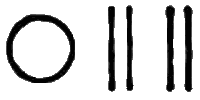

Symp. Each febrile paroxysm is of three periods or stages—the cold, the hot, and the sweating stage, and these occur in regular succession. The cold stage commences with great languor and aversion to motion; a sense of coldness down the back soon follows; then the extremities become cold, the fingers shrunken, and the nails blue; the skin assumes that peculiar condition which is commonly known as ‘goose-skin,’ the patient shivers, his teeth chatter, and he is glad to draw close to the fire or envelop himself in blankets. After this state of things has continued for a greater or less time, the heat of the surface begins to return, the patient has flushings and becomes warmer and warmer, and ultimately the whole surface is of a dry burning heat; intense thirst, restlessness, severe headache, and sometimes delirium, characterise this second or hot stage. After this stage has continued for some time, another change comes over the patient; moisture appears on the face and forehead, the harsh and hot skin becomes soft, and at last a copious sweat breaks out over the whole surface. This is the third or sweating stage, and after it has passed, the several functions of the system return to their ordinary condition. The paroxysm may return daily (QUOTIDIAN AGUE); or every other day (TERTIAN A.); or every fourth day, including that of the first attack (QUARTAN A.).